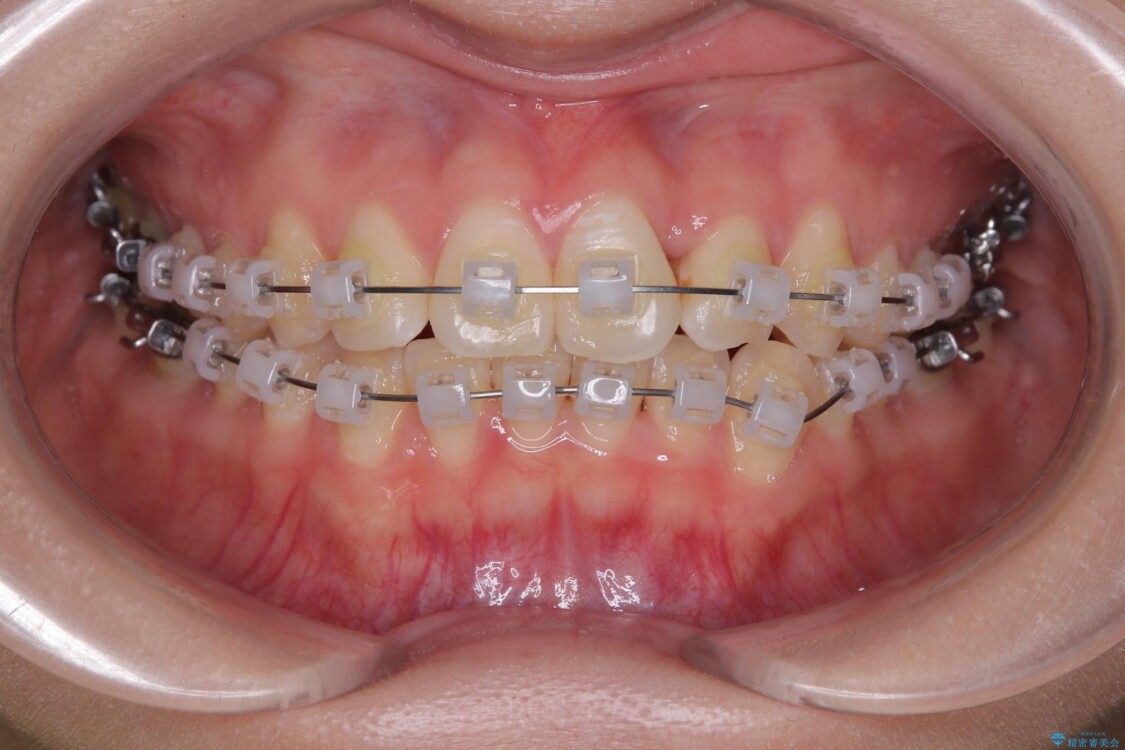

治療方法としては、装置の目立ちにくさと費用面のバランスを考慮して、プラスチック製のクリアブラケットとメタルワイヤーを組み合わせた矯正装置を使用することにしました。

治療途中

• 前歯のねじれ・ガタガタを10か月で改善!20代女性の矯正治療|クリアブラケットでむし歯になりにくい歯並びへ改善 治療途中画像